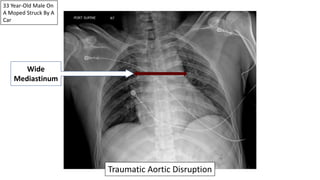

33 Year-Old Male On

A Moped Struck By A

Car

Wide

Mediastinum

Traumatic Aortic Disruption